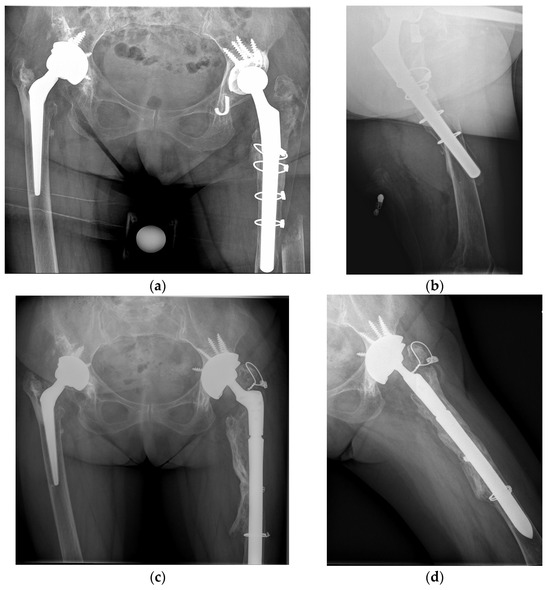

2.1.2. Surgical Technique